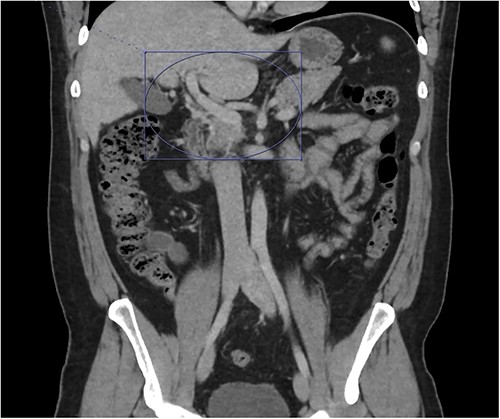

At home, the patient continued to do well and remained free of abdominal pain. He was tolerating a normal diet without emesis and was having normal bowel function. His outpatient CT scan 3 months after discharge demonstrated near resolution of his subocclusive PV and SMV thrombus and attenuated periappendiceal inflammation (Figs 3 and 4). Given the patient’s clinical stability and benign radiographic findings, the patient was scheduled for a laparoscopic appendectomy.

Only a slender portion of thrombus remains in the main portal vein; the previously seen splenic vein thrombosis has largely resolved (not well visualized).